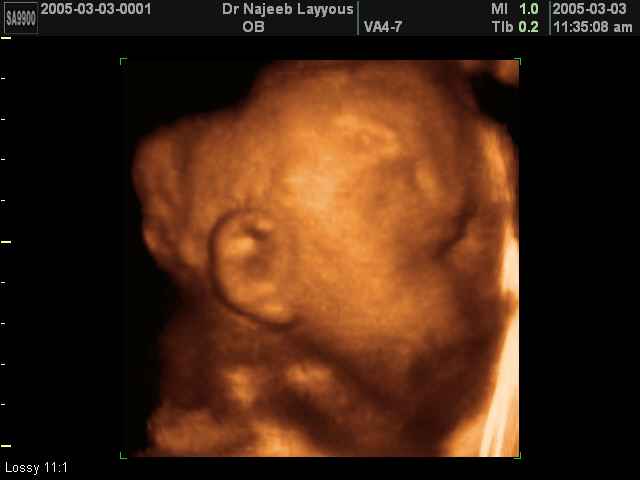

- 3D Fetal Profile Ultrasound Scan Photos